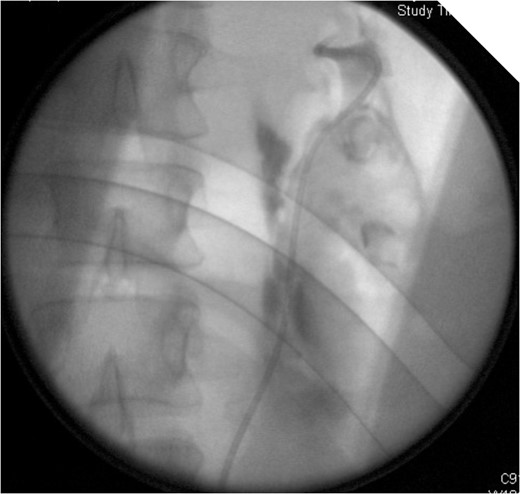

On table Pyelogram confirmed intact left collecting system and ureter.